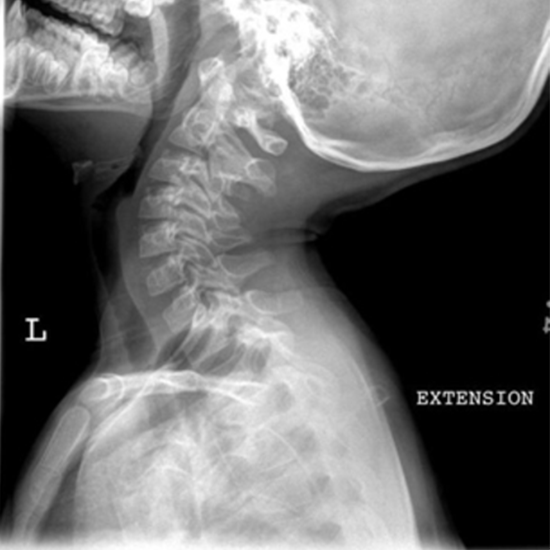

X-Ray CV Junction Extension/Flexion

The C1-C2 test is an X-ray that shows the upper cervical spine, especially the C1 and C2 vertebrae, and the soft tissues around them (skin and muscles). Vertebral pain at C1-C2 can range from a dull ache to a sharp, burning pain in the neck. C1-C2 pain can last for a short time or for a long time.

The doctor gives you this test to determine if you have a broken C1 vertebra (C1 Burst Fracture) or a broken C2 vertebra (C2 Odontoid Fracture). To find out if the ligaments around the vertebra are hurt.